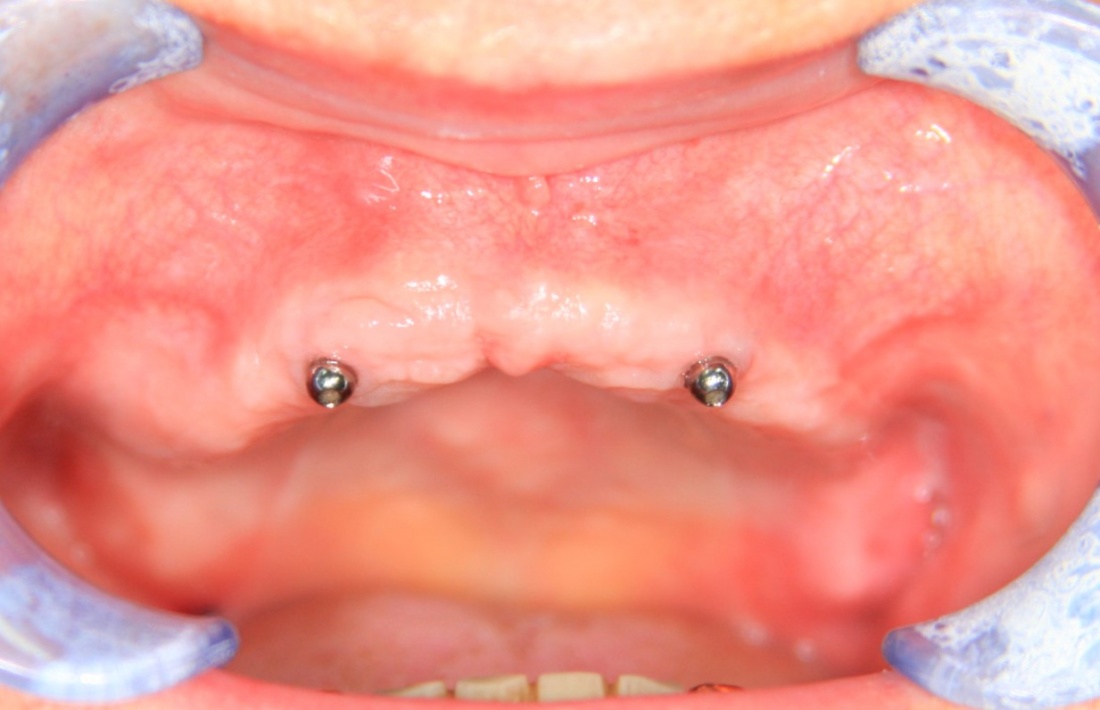

80-летняя бабушка жалуется на то, что у неё съемный протез выпадает, ей перед подругами по лавочке стыдно. И она ожидает, что мы придумаем какую-нибудь штуку, которая поможет её протезу держаться на челюсти и не выпадать.

Скажите, каким будет оптимальное решение в её случае? 2 импланта, шариковые абатменты или локаторы:

Просто фиксируем существующий протез к имплантам — и всё! Бабушка счастлива!